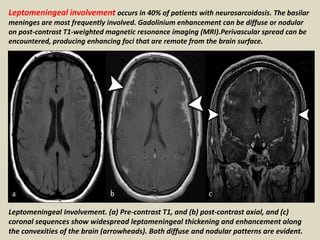

Leptomeningeal involvement occurs in 40% of patients with neurosarcoidosis. The basilar

meninges are most frequently involved. Gadolinium enhancement can be diffuse or nodular

on post-contrast T1-weighted magnetic resonance imaging (MRI).Perivascular spread can be

encountered, producing enhancing foci that are remote from the brain surface.

Leptomeningeal Involvement. (a) Pre-contrast T1, and (b) post-contrast axial, and (c)

coronal sequences show widespread leptomeningeal thickening and enhancement along

the convexities of the brain (arrowheads). Both diffuse and nodular patterns are evident.